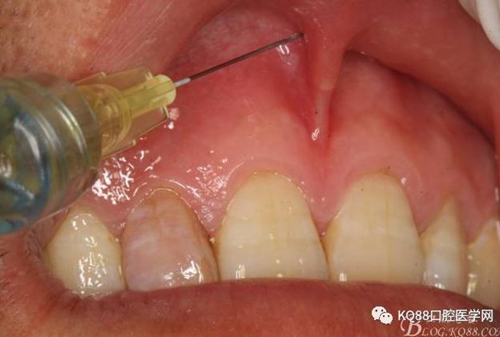

圖4. 唇腭側(cè)局部浸潤麻醉行根尖囊腫摘除術(shù)+根管倒充填。唇側(cè)浸潤要求進針深度比正常麻醉深度要深點,因為還有囊腫的摘除。

圖5.腭乳頭浸潤麻醉。注意:腭乳頭粘膜發(fā)白即可